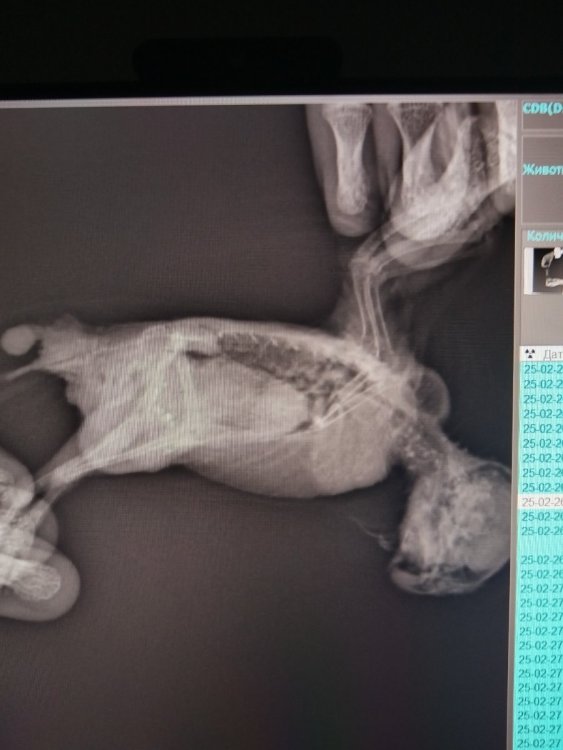

Добрый день , столкнулись с такой проблемой: волнистик не питается самостоятельно, похудел, стали наблюдать, что не может расщелкнуть зерно, на данный момент кормим детскими кашами со шприца , делали в клинике рентген( прикрепляю ) сказали , что все очень плохо, посоветовали усыпить, но в нашем сердце живет надежда , что получится птичку спасти , может кто-то в этом разбирается получше , хочется хотя бы еще одно мнение по поводу снимков , почитала в интернете , под критерии правильно проведенного исследования, он к сожалению, не подходит

Сказала, что точно не уверена, но похоже на опухоль

В клинике нам сказали , что на верхней стороне хвоста  , это вырост копчиковой железы( если я не ошибаюсь ) и что это не страшно, а вот по внутренним органам сказали , что все плохо

И вырост-это Н/О. Т.к. сама копчиковая железа выглядит по другому.